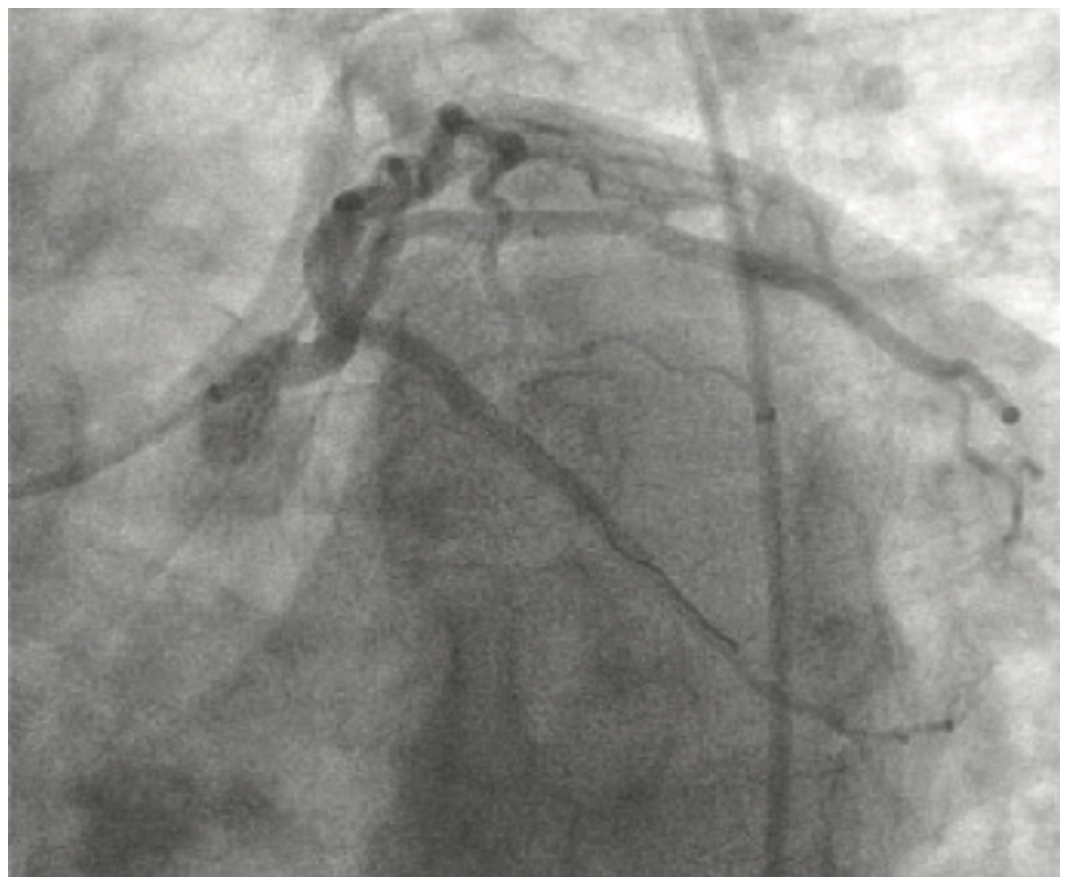

Given the anticipation for the need of significant support, this case was performed from a right common femoral artery access with a 6 French (Fr) extra backup (XB) 3.5 guiding catheter through a 6 Fr × 45 cm sheath. Figure 3 and Video 1 show a left anterior oblique (LAO) projection of the left coronary artery (LCA) system. The unusual aspect of the LCA anatomy is the tortuous mid left main (LM) segment approaching an 80° angle, which then gives rise to the left circumflex (LCx) artery at a very steep obtuse angle in the opposite direction. The addition of the two angles of the mid-LM tortuosity and the LCx artery takeoff comes close to 290°. This interesting anatomy, combined with the distal aspect of the LCx lesion extending to a small size third obtuse marginal branch (OM3), made this case relatively complex.

Figure 4 and Video 2A and Video 2B show the LCx in antero-posterior (AP) caudal and right anterior oblique (RAO) caudal projections. Due to the cumulative 290° angle between the takeoff of the proximal LM segment and the direction of the LCx artery, it was not possible to advance a wire past the proximal LCx artery segment. Four different wires were used (Sion Blue [Asahi Intecc], Whisper extra support [ES] [Abbott Vascular], Choice Extra Support [Boston Scientific], and Whisper medium support [MS] [Abbott Vascular]) without successfully passing beyond the proximal LCx segment, due to recurrent wire prolapse back into the ramus branch once the wires made the turn into the mid LCx segment. The friction caused by the LCx angulation eliminated the transmission of torque to the tip of the wire despite the use of polymer-jacketed and hydrophilic wires (Figure 5 and Video 3). We did not think that advancing an over-the-wire low-profile balloon or straight microcatheter would help in this situation, because there was not enough wire purchase into the vessel to advance these devices without a recurrent wire prolapse.